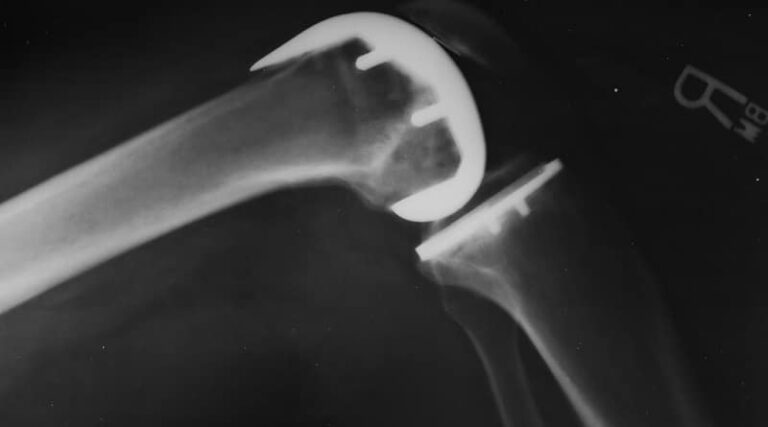

La protesizzazione del ginocchio consiste nel ricostruire chirurgicamente l’articolazione formata…